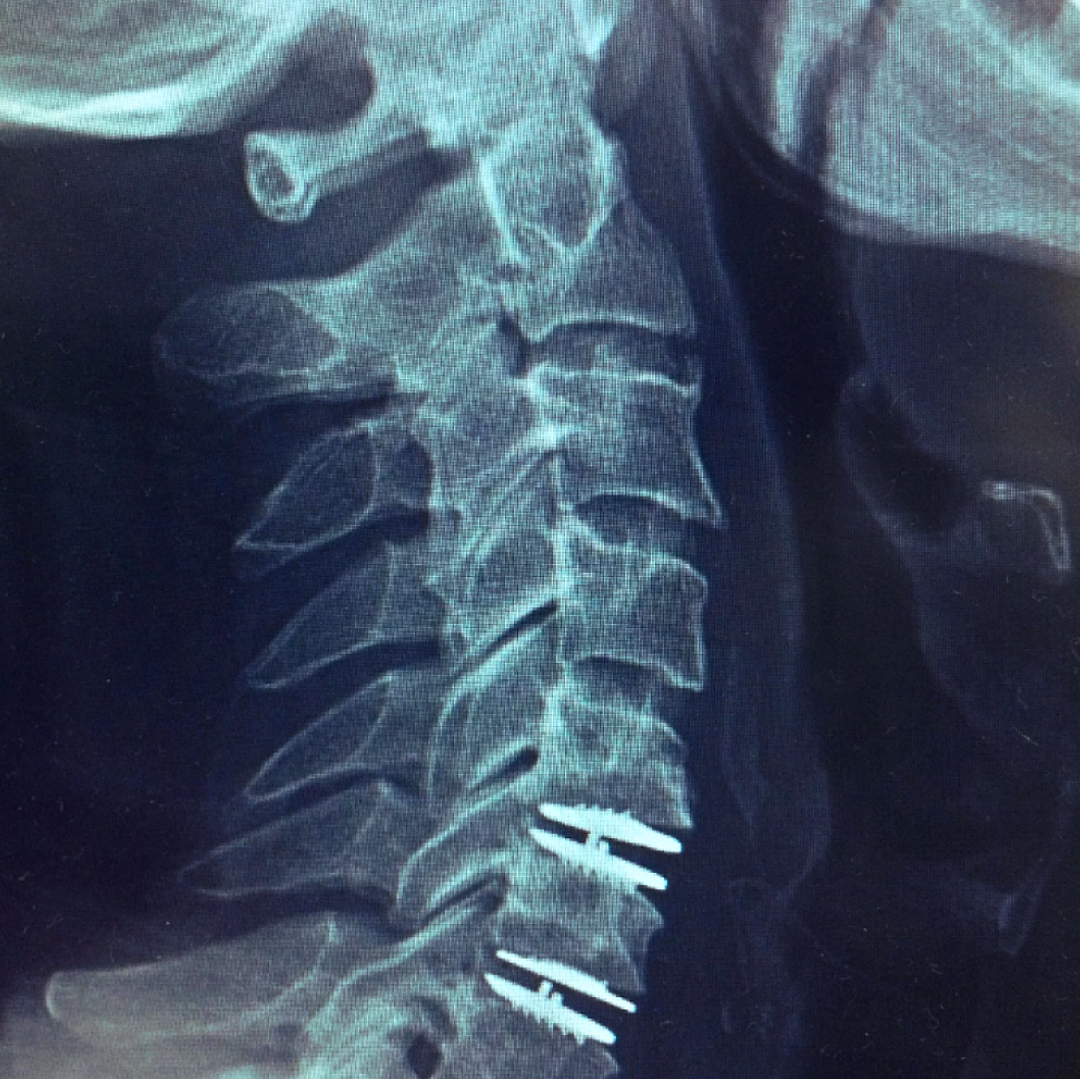

استبدال الديسك العنقي الاصطناعي

جراحة استبدال الديسك العنقي تنطوي على إزالة الديسك العنقي المصاب واستبداله بديسك اصطناعي

عندما يضيق المسافة بين فقرات عنق الرحم، قد يؤدي ذلك إلى دفع جزء من فقرات العنق الرحم إلى الحبل الشوكي، مما يسبب الألم والخدر والضعف. وعندما تفشل العلاجات غير الجراحية في تخفيف هذه الأعراض، قد يكون هناك حاجة لإجراء جراحة استبدال الديسك الاصطناعي.